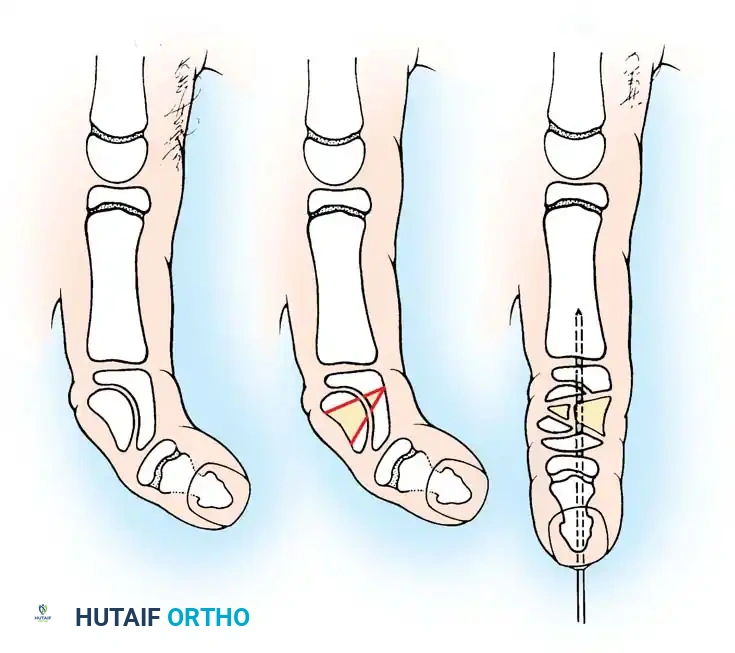

CAMPTODACTYLY

Camptodactyly (from the Greek kamptos meaning bent, and daktylos meaning finger) is a non-traumatic, progressive flexion deformity of the proximal interphalangeal (PIP) joint. It predominantly involves the little finger.

This condition must be distinguished from clinodactyly, which is a radioulnar deviation of the digit (usually at the distal interphalangeal joint). Camptodactyly occurs in less than 1% of the general population but accounts for nearly 6.9% of congenital hand anomalies.

The etiology is multifactorial, and virtually every anatomical structure crossing the volar aspect of the PIP joint has been implicated:

* Fascial Bands: Kilgore and Graham identified stout, abnormal fascial bands associated with the Landsmeer (retinacular) ligament.

* Lumbrical Anomalies: McFarlane, Curry, and Evans found abnormal insertions of the lumbrical tendon into the FDS tendon, the MCP joint capsule, or the adjacent extensor expansion in 100% of their operative cases.

* Flexor/Extensor Imbalance: Millesi proposed that the deformity arises from a relative dynamic imbalance between the flexors and extensors.

* FDS Shortening: Smith and Kaplan suggested a relative shortening of the FDS muscle-tendon unit. This is supported clinically when the PIP flexion deformity corrects upon simultaneous flexion of the wrist.

* Other Factors: Contractures of the volar plate, accessory collateral ligaments, and insufficient palmar skin.

Operative Indications:

* Progressive deformity >40 degrees interfering with function.

* Young children whose deformity corrects with wrist flexion (indicates isolated FDS tightness amenable to simple release).

* Older children with fixed deformities requiring complex structural release.

Preoperative planning diagram for a comprehensive volar release, highlighting the structures contributing to the flexion contracture.

TECHNIQUE 76-53: Comprehensive Tendon Release (Smith's Approach)

Smith emphasized a "unifying theory" of camptodactyly, advocating that all abnormal structures must be systematically addressed. The frequency of involvement includes skin (100%), FDS (66%), retinaculum cutis (55%), and lumbricals (22%).

- Incision and Skin Lengthening:

Make a volar linear incision over the affected digit and convert it to multiple Z-plasties. Ensure the central limbs of the Z-plasties are placed precisely over the flexion creases of the joints to prevent secondary scar contracture.